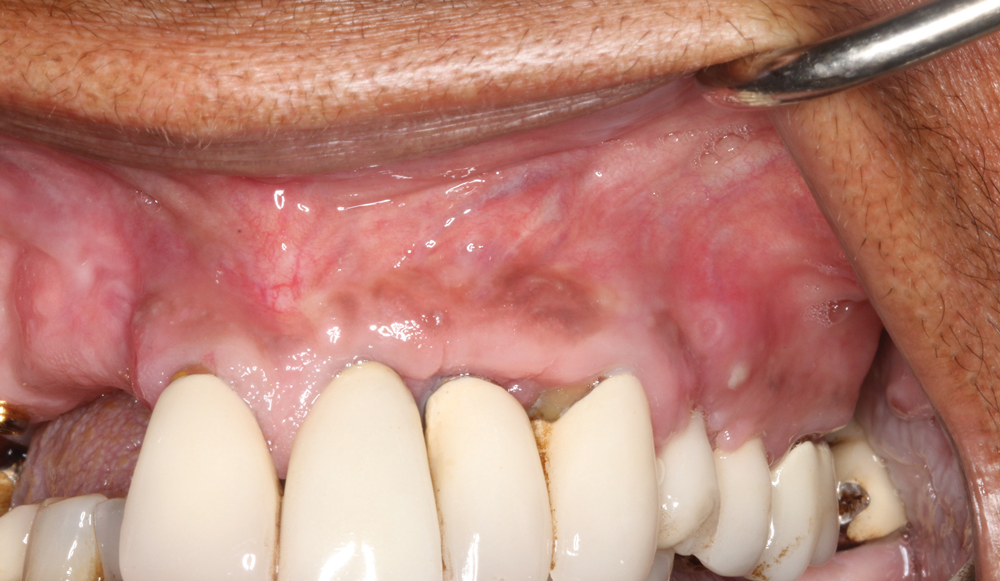

In this case, a dental implant that had been placed 10 years prior was functional, stable, and esthetically acceptable to the patient. However, a significant fistula was present on the facial-apical aspect of the ridge in the maxillary lateral incisor area. This area was painfully sensitive to touch and demonstrated purulence when squeezed. To evaluate the lesion, first, a conventional digital radiograph was acquired, which revealed an apical radiolucency at the apex of the implant (Figure 1). Further analysis using cone-beam computed tomography (CBCT) demonstrated a fistula from that site to the oral environment (Figure 2). Treatment options were discussed, including removal of the implant, followed by grafting, a healing period, and replacement of the implant and implant-retained crown. If this option was selected, a transitional appliance would need to be created. Another option was to attempt to salvage the implant and implant crown by treating the infection and grafting the site to create a new boney wall and eliminate the fistula. Ultimately, the patient accepted this option to attempt to salvage the fixture and crown.

(1.) Preoperative radiographic evaluation demonstrating a large radiolucency at the apical third of the body of an implant fixture replacing the patient’s maxillary left lateral incisor. The implant was stable, and the prosthesis was deemed esthetically acceptable by the patient.

Figure 1